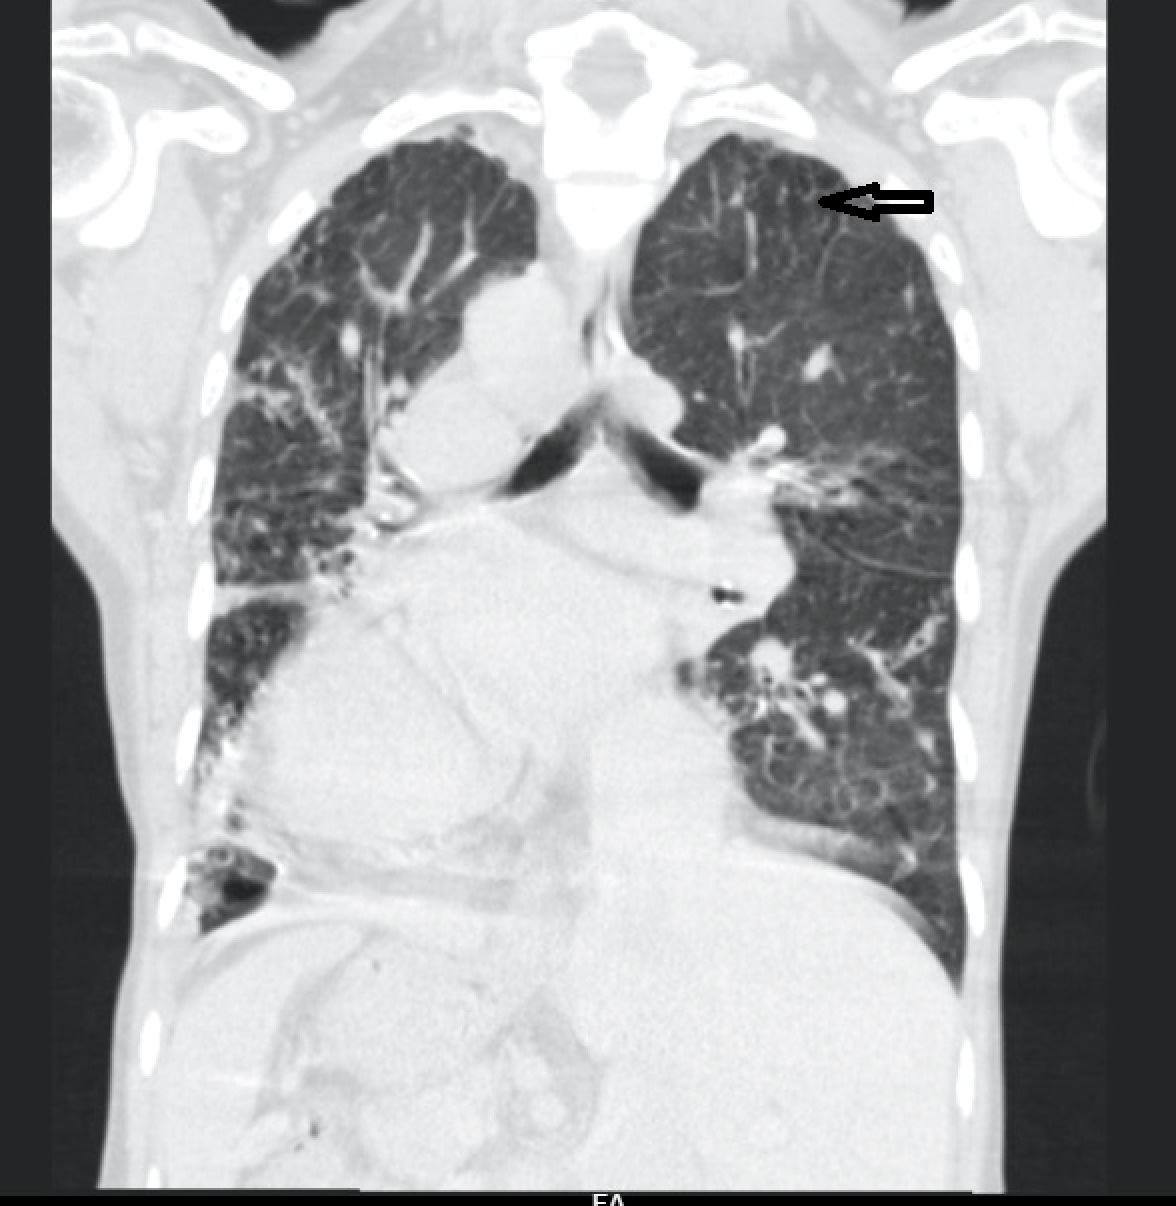

For further evaluation, a contrast-enhanced CT scan of the thorax was done, which revealed varicose bronchiectasis involving the right middle lobe [Table/Fig-2,3] and lingular bronchiectasis of the left upper lobe [Table/Fig-4]. Brochoscopic alveolar lavage fluid was sent for analysis, which grew strains of Mycobacterium avium complex (MAC). A 2D ECHO was done, which showed evidence of severe pulmonary artery hypertension and gross tricuspid regurgitation, with good right ventricular function. Also, the patient was asked if she had the habit of voluntarily suppressing cough, to which her response was affirmative. She was a habitual cough suppressor, as a mechanism to prevent episodes of upper abdominal pain on recurrent cough episodes. With all these findings observed, we concluded that it was a case of ‘Lady Windermere Syndrome’. We started the patient on a 3-drug regimen (rifampicin, ethambutol and clarithromycin). After 2 months of follow up, the patient’s symptoms had slightly improved [Table/Fig-5].

CECT thorax showing lingular bronchiectasis of left upper lobe.